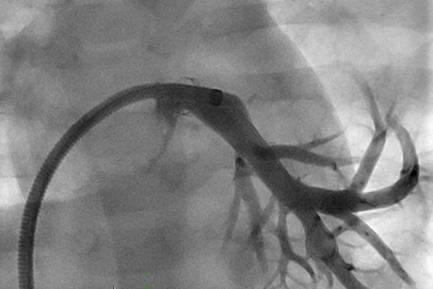

Figure 2. Residual stenosis of the left lower pulmonary vein following ITSF.